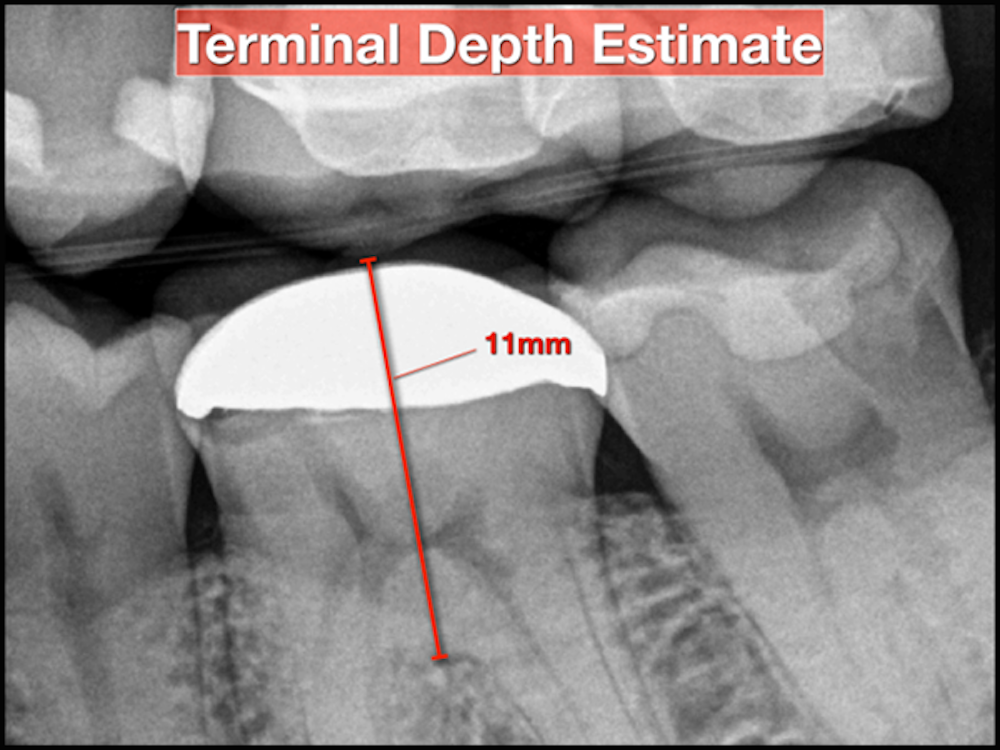

Before initiating treatment, an estimate can be made from the tooth’s occlusal surface (or incisal edge) to various levels within the tooth. This estimate represents a “target vertical depth” and can assist with endodontic access when measured to the roof of the pulp chamber (Fig. 1). In multi-rooted teeth, an additional “terminal depth estimate,” measured to the furcation, could help avoid iatrogenic perforation (Fig 2).

A bitewing radiograph is considered to be the most spatially accurate and dimensionally stable image with respect to 2-dimensional radiography, making it ideal to estimate the depth when treating posterior teeth. Estimates for anterior teeth must be determined from the slightly more distorted periapical radiograph (Fig 3). This visual exercise can also influence case selection.